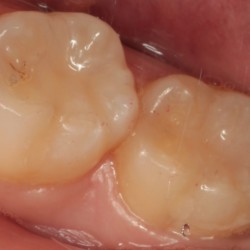

歯とつめものの隙間の虫歯

-

コンポジットレジン修復後